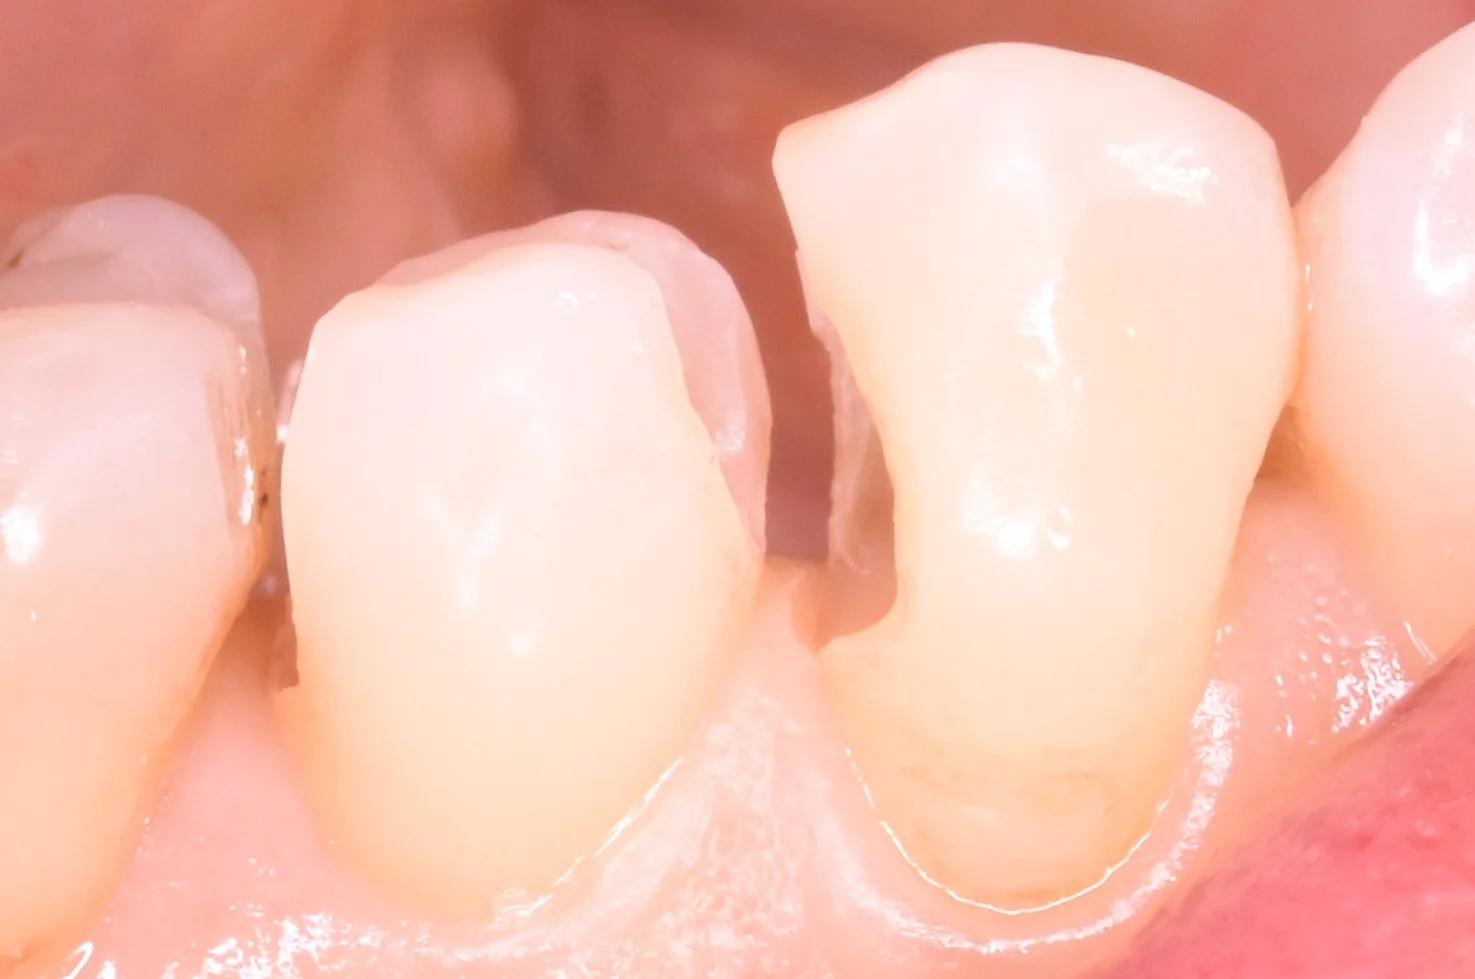

想定よりも大きく歯が無くなってしまっていたので、今回、側面の写真も撮りました。

それがこちらになります。

こう見るとどれほど大きな虫歯だったのか想像できるかと思います。